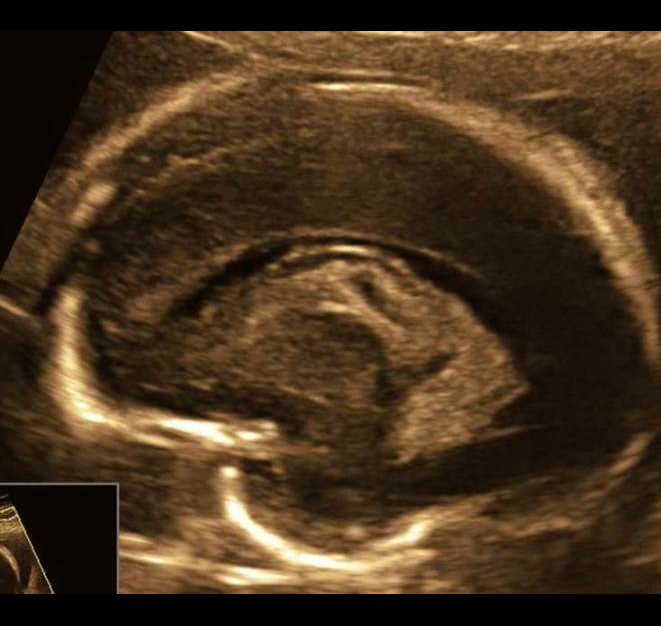

Вопрос 4

Срок 22 недели 5 дней. Вентрикуломегалия тяжелой степени. Пол плода — женский. В какой части головного мозга скрывается основной диагноз?

Трансцеребеллярный скан и 3Д режимы

Ответ на вопрос 4

- Поиск основного диагноза нужно вести в области задней черепной ямки (смотрим НАЗАД).

- Очевидно, что полушария мозжечка уменьшены в размерах (фокальная гипоплазия полушарий мозжечка), червь сформирован правильно (об этом подробно поговорим на второй лекции).

- При консультировании — обязательно предлагаем инвазивную диагностику с лабораторным исследованием молекулярного кариотипа (ХММА).